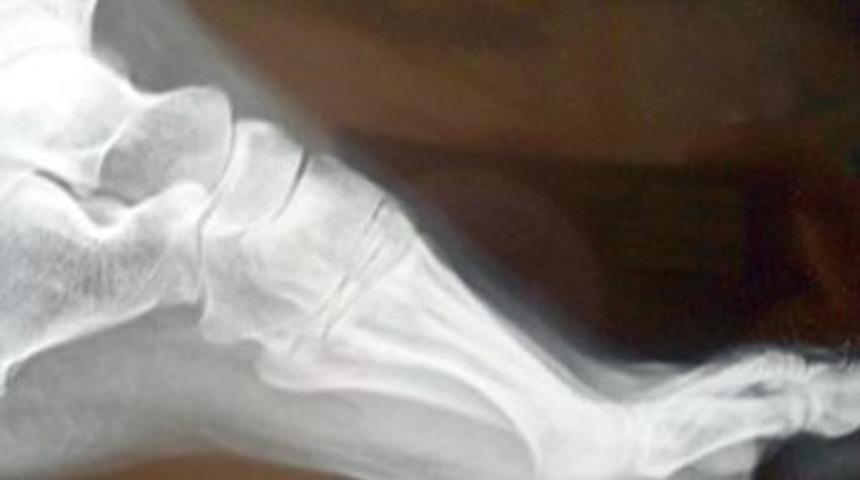

Konya'da 21 yaşındaki Elif Banu Kara'nın eşarbını bağlarken hapşırması sonucu 2 yıl önce yuttuğu iğne, ayak başparmağından çıktı.

Kara'nın yuttuğunu bile unuttuğu iğne, vitrin camının kırılması sonucu gittiği hastanede çekilen röntgen filminde belirlendi. Biri et diğeri damar içinde iki parça halindeki iğne, operasyonla alındı.

Konya'da oturan Elif Banu Kara, 2 yıl önce eşarbını bağlarken kullandığı iğneyi ağzına aldı. Bu sırada birden hapşıran Kara, ağzında tuttuğu iğneyi yuttu. Yaşadığı olaydan sonra herhangi bir rahatsızlık duymayan Kara, bir hafta sonra hastaneye giderek iğne yuttuğunu söyledi ve muayene oldu. Ancak vücudundaki iğnenin yeri tespit edilemedi. Bu şekilde hayatına devam eden Elif Banu Kara, yaklaşık 20 gün önce evde temizlik yaparken vitrinin camı kırıldı. Farkında olmadan yerlere saçılan cam parçalarının üzerine basan Kara, ayağına cam kırığının girdiğini düşünerek hastaneye gitti. Burada çekilen röntgen filmi sonrası sol ayak başparmağının başlangıç noktasında, cam parçası yerine iğne tespit edildi. 2 yıl önce yuttuğu iğnenin ayak başparmağının altına kadar geldiğini gören Kara, şaşkınlık yaşadı. Kara, Özel Kızılay Hastanesi'nde ameliyata alındı. Ayak başparmağının altında kırıldığı tespit edilen iki parça halindeki iğnenin bir parçası et, diğeri de damar içinden çıraktıldı.